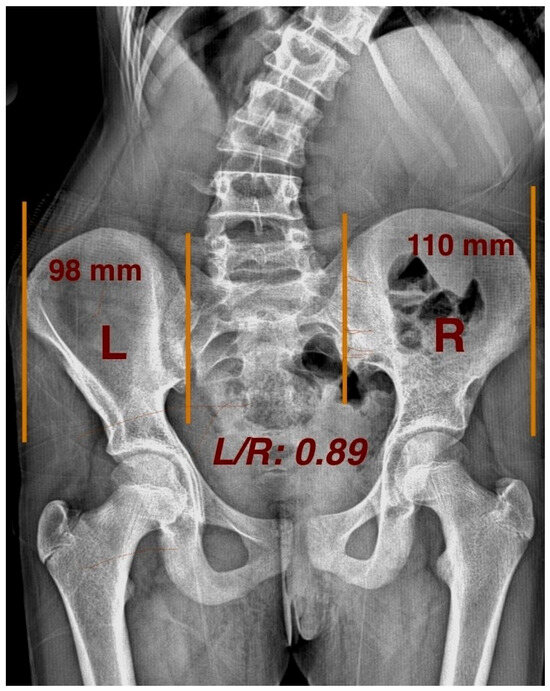

The pelvic axial rotation (PAR) direction was assessed using the method described by Gum et al. [8]. Studies have verified asymmetrical ilium widths between the convex and concave sides in untreated AIS patients, signifying considerable pelvic rotation [3]. On AP radiographs, the horizontal distance between a vertical reference line drawn from the anterior superior iliac spine (ASIS) and the posterior inferior iliac spine (PIIS) at the corresponding sacroiliac joint was measured to determine the width of the left (L) and right (R) ala ossis ilii (Figure 4).

The PAR direction was then determined by calculating the L/R ratio as follows:

To exclude measurement bias and physiologic PAR, we defined the presence of PAR when the L/R ratio was <0.95 or >1.05.

R-PAR: L/R < 0.95, indicating pelvic rotation toward the right;

L-PAR: L/R > 1.05, indicating pelvic rotation toward the left.

Figure 4. Measuring pelvic axial rotation, and L/R ratio on radiograph.